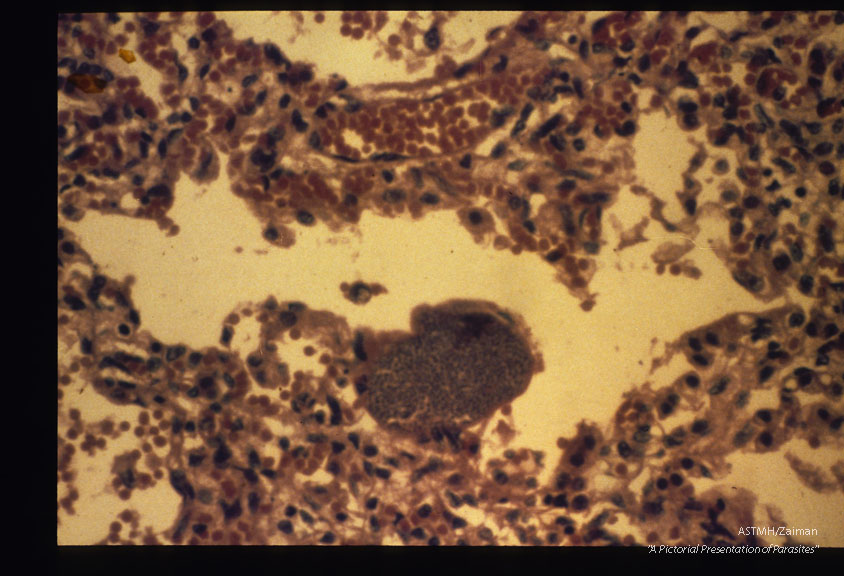

A large parasitized cell protrudes into an alveolus of this patient suffering from congenitally transmitted Chagas' disease.

Trypanosoma cruzi

Description: A large parasitized cell protrudes into an alveolus of this patient suffering from congenitally transmitted Chagas' disease.